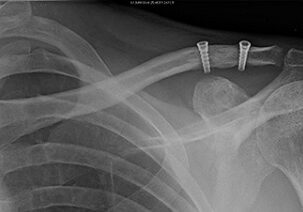

2. AC Joint Stabilization:

• Stabilization procedures involve using hardware such as screws or suture anchors to stabilize the AC joint and restore alignment.

• Results can include reduced pain, improved shoulder function, and decreased risk of recurrent dislocations or subluxations.

• Patients may require a period of immobilization followed by gradual rehabilitation to regain strength and mobility in the shoulder joint.